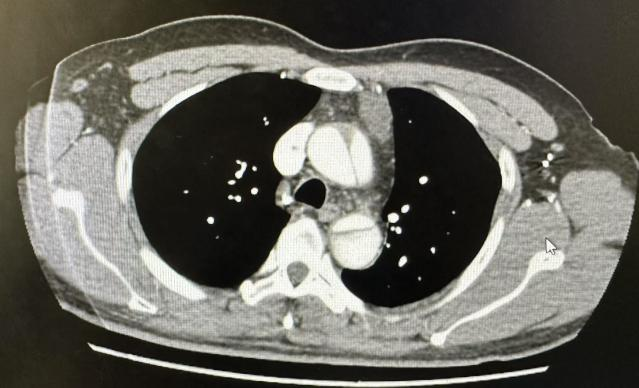

入院后,胸心血管外科团队立即对患者病情展开全面评估。胸部CTA显示:升主动脉夹层,累及范围广泛,右侧颈总动脉均受夹层累及,降主动脉夹层已经形成瘤样扩张。随时可能出现破裂而危及生命。

术前胸主动脉CTA